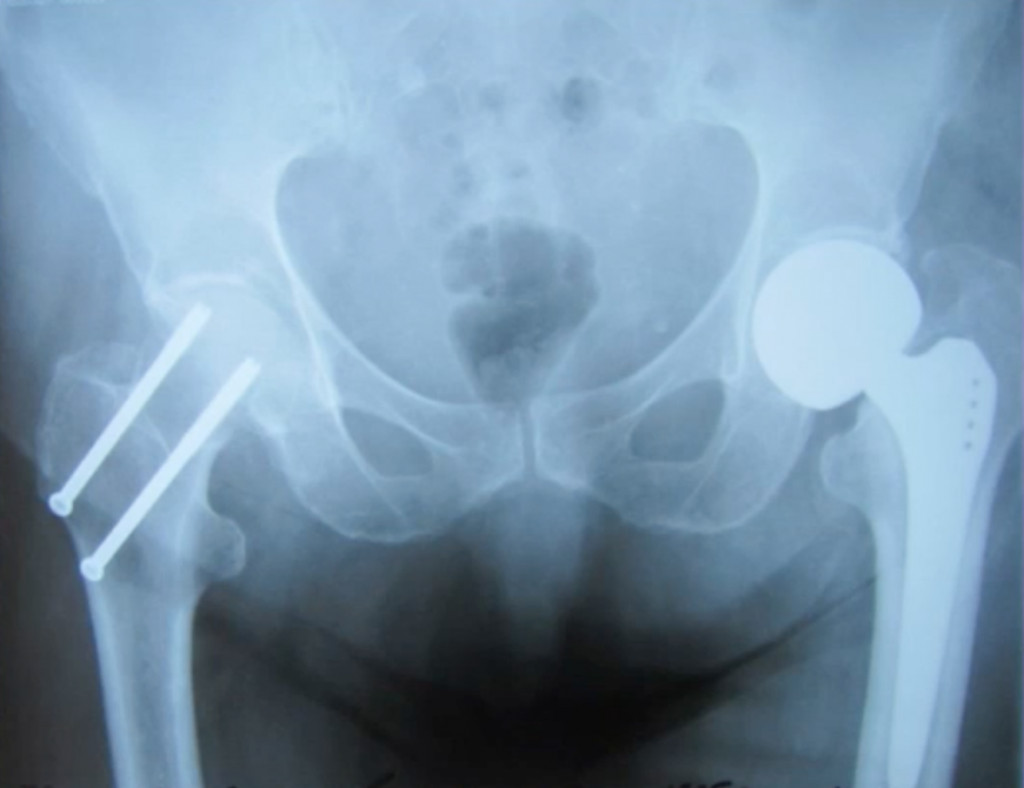

ΠΒ ΠΠ»ΠΈΠ½ΠΈΡΠ΅ΡΠΊΠΎΠΌ Π³ΠΎΡΠΏΠΈΡΠ°Π»Π΅ Π½Π°Β Π―ΡΠ·Π΅ ΠΌΡΒ Π²ΡΠΏΠΎΠ»Π½ΡΠ΅ΠΌ Π½Π΅ΡΠΊΠΎΠ»ΡΠΊΠΎ Π²ΠΈΠ΄ΠΎΠ² ΠΎΠΏΠ΅ΡΠ°ΡΠΈΠΉ. ΠΒ Π·Π°Π²ΠΈΡΠΈΠΌΠΎΡΡΠΈ ΠΎΡΒ Π²ΠΎΠ·ΡΠ°ΡΡΠ° ΠΈΒ ΠΎΠ±ΡΠ°Π·Π° ΠΆΠΈΠ·Π½ΠΈ ΠΌΡΒ Π·Π°ΠΌΠ΅Π½ΡΠ΅ΠΌ ΠΈΠ»ΠΈ Π²Π΅ΡΡ ΡΡΡΡΠ°Π² ΠΏΠΎΠ»Π½ΠΎΡΡΡΡ (Π΄Π»Ρ Π±ΠΎΠ»Π΅Π΅ Π°ΠΊΡΠΈΠ²Π½ΡΡ ΠΏΠ°ΡΠΈΠ΅Π½ΡΠΎΠ²), Π»ΠΈΠ±ΠΎ ΡΠΎΠ»ΡΠΊΠΎ ΡΠ»ΠΎΠΌΠ°Π½Π½ΡΡ ΡΠ΅ΠΉΠΊΡ ΠΈΒ Π³ΠΎΠ»ΠΎΠ²ΠΊΡ (Π΄Π»Ρ ΠΌΠ°Π»ΠΎΠΏΠΎΠ΄Π²ΠΈΠΆΠ½ΡΡ ΠΏΠ°ΡΠΈΠ΅Π½ΡΠΎΠ²). Π Π°Π·ΡΠ΅Π· Π²Β ΠΎΠ±Π»Π°ΡΡΠΈ ΡΠ°Π·ΠΎΠ±Π΅Π΄ΡΠ΅Π½Π½ΠΎΠ³ΠΎ ΡΡΡΡΠ°Π²Π° ΡΠΎΡΡΠ°Π²Π»ΡΠ΅Ρ ΠΎΠΊΠΎΠ»ΠΎ 15Β ΡΠΌ. ΠΠΏΠ΅ΡΠ°ΡΠΈΡ Π΄Π»ΠΈΡΡΡ ΠΎΡΒ 30Β Π΄ΠΎΒ 90Β ΠΌΠΈΠ½. ΠΡΠΎΠ²ΠΎΠΏΠΎΡΠ΅ΡΡΒ β ΠΎΡΒ 50Β Π΄ΠΎΒ 500Β ΠΌΠ». ΠΠΏΠ΅ΡΠ°ΡΠΈΡ Π²ΡΠΏΠΎΠ»Π½ΡΠ΅ΡΡΡ ΠΏΠΎΠ΄ ΡΠΏΠΈΠ½Π°Π»ΡΠ½ΠΎΠΉ Π°Π½Π΅ΡΡΠ΅Π·ΠΈΠ΅ΠΉ.

- ΠΎΠ΄Π½ΠΎΠΏΠΎΠ»ΡΡΠ½ΠΎΠ΅ ΠΈΠ»ΠΈ Π΄Π²ΡΡ ΠΏΠΎΠ»ΡΡΠ½ΠΎΠ΅ ΡΠ½Π΄ΠΎΠΏΡΠΎΡΠ΅Π·ΠΈΡΠΎΠ²Π°Π½ΠΈΠ΅.

ΠΠ°ΠΈΠ±ΠΎΠ»Π΅Π΅ Π±Π»Π°Π³ΠΎΠΏΡΠΈΡΡΠ½ΡΠ΅ ΠΏΡΠΎΠ³Π½ΠΎΠ·Ρ ΠΏΠΎΡΠ»Π΅ ΡΠ½Π΄ΠΎΠΏΡΠΎΡΠ΅Π·ΠΈΡΠΎΠ²Π°Π½ΠΈΡ, ΠΏΠΎΠ·Π²ΠΎΠ»ΡΡΡΠ΅Π³ΠΎ ΠΌΠ°ΠΊΡΠΈΠΌΠ°Π»ΡΠ½ΠΎ ΡΠΎΡ ΡΠ°Π½ΠΈΡΡ Π΄Π²ΠΈΠ³Π°ΡΠ΅Π»ΡΠ½ΡΡ Π°ΠΊΡΠΈΠ²Π½ΠΎΡΡΡ ΠΏΠ°ΡΠΈΠ΅Π½ΡΠ°.

Π£ ΠΏΠΎΠΆΠΈΠ»ΡΡ

ΠΈΡΡΡΠ³ΠΈΡΠ΅ΡΠΊΠΈΠΌ ΠΏΡΡΠ΅ΠΌ. ΠΠΎ Π²ΡΠ΅ΠΌΡ ΠΎΠΏΠ΅ΡΠ°ΡΠΈΠΈ ΠΎΡΡΠ΅ΠΎΡΠΈΠ½ΡΠ΅Π·Π° ΡΠΎΠΏΠΎΡΡΠ°Π²Π»ΡΡΡ ΠΎΠ±Π»ΠΎΠΌΠΊΠΈ ΠΊΠΎΡΡΠΈ ΠΈ ΡΠΊΡΠ΅ΠΏΠ»ΡΡΡ ΠΈΡ

ΠΌΠ΅ΡΠ°Π»Π»ΠΈΡΠ΅ΡΠΊΠΈΠΌΠΈ ΠΏΠ»Π°ΡΡΠΈΠ½Π°ΠΌΠΈ. Π Π½Π΅ΠΊΠΎΡΠΎΡΡΡ

(ΠΏΡΠΈ ΡΠ°Π·Π²ΠΈΡΠΈΠΈ Π°ΡΠ΅ΠΏΡΠΈΡΠ΅ΡΠΊΠΎΠ³ΠΎ Π½Π΅ΠΊΡΠΎΠ·Π°, ΡΠΈΠ»ΡΠ½ΠΎΠΌ ΡΠ°Π·Π΄ΡΠΎΠ±Π»Π΅Π½ΠΈΠΈ ΠΊΠΎΡΡΠΈ) ΠΌΠΎΠΆΠ΅Ρ Π²ΠΎΠ·Π½ΠΈΠΊΠ½ΡΡΡ Π½Π΅ΠΎΠ±Ρ

ΠΎΠ΄ΠΈΠΌΠΎΡΡΡ Π² ΡΠ½Π΄ΠΎΠΏΡΠΎΡΠ΅Π·ΠΈΡΠΎΠ²Π°Π½ΠΈΠΈ.